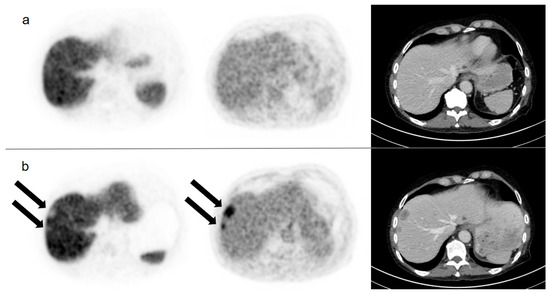

| 3 | >10 | DBMI | 1 | OSS | − | − | − |

| 4 | DBMI | DBMI | 2 | HEP * | − | − | − |

| 7 | >10 | >10 | n.a. | n.a. | >10 | 1 | OSS |

| 10 | >3 but <10 | >3 but <10 | 4 | HEP **, PeC | >10 | 7 | HEP **, PeC |

| 14 | >10 | >10 | n.a. | n.a. | >10 | 3 | HEP |

| 23 | >10 | >10 | 1 | LN | >10 | 9 | LN |